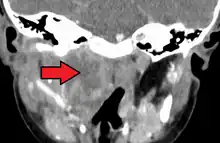

| A lateral neck X-ray demonstrating soft tissue swelling in front of the vertebrae (marked by the arrow) as seen in a person with a retropharyngeal abscess. | |

X-ray of the neck 80% of the time shows swelling of the retropharyngeal space in affected individuals. If the retropharyngeal space is more than half of the size of the C2 vertebra, it may indicate retropharyngeal abscess.[7]